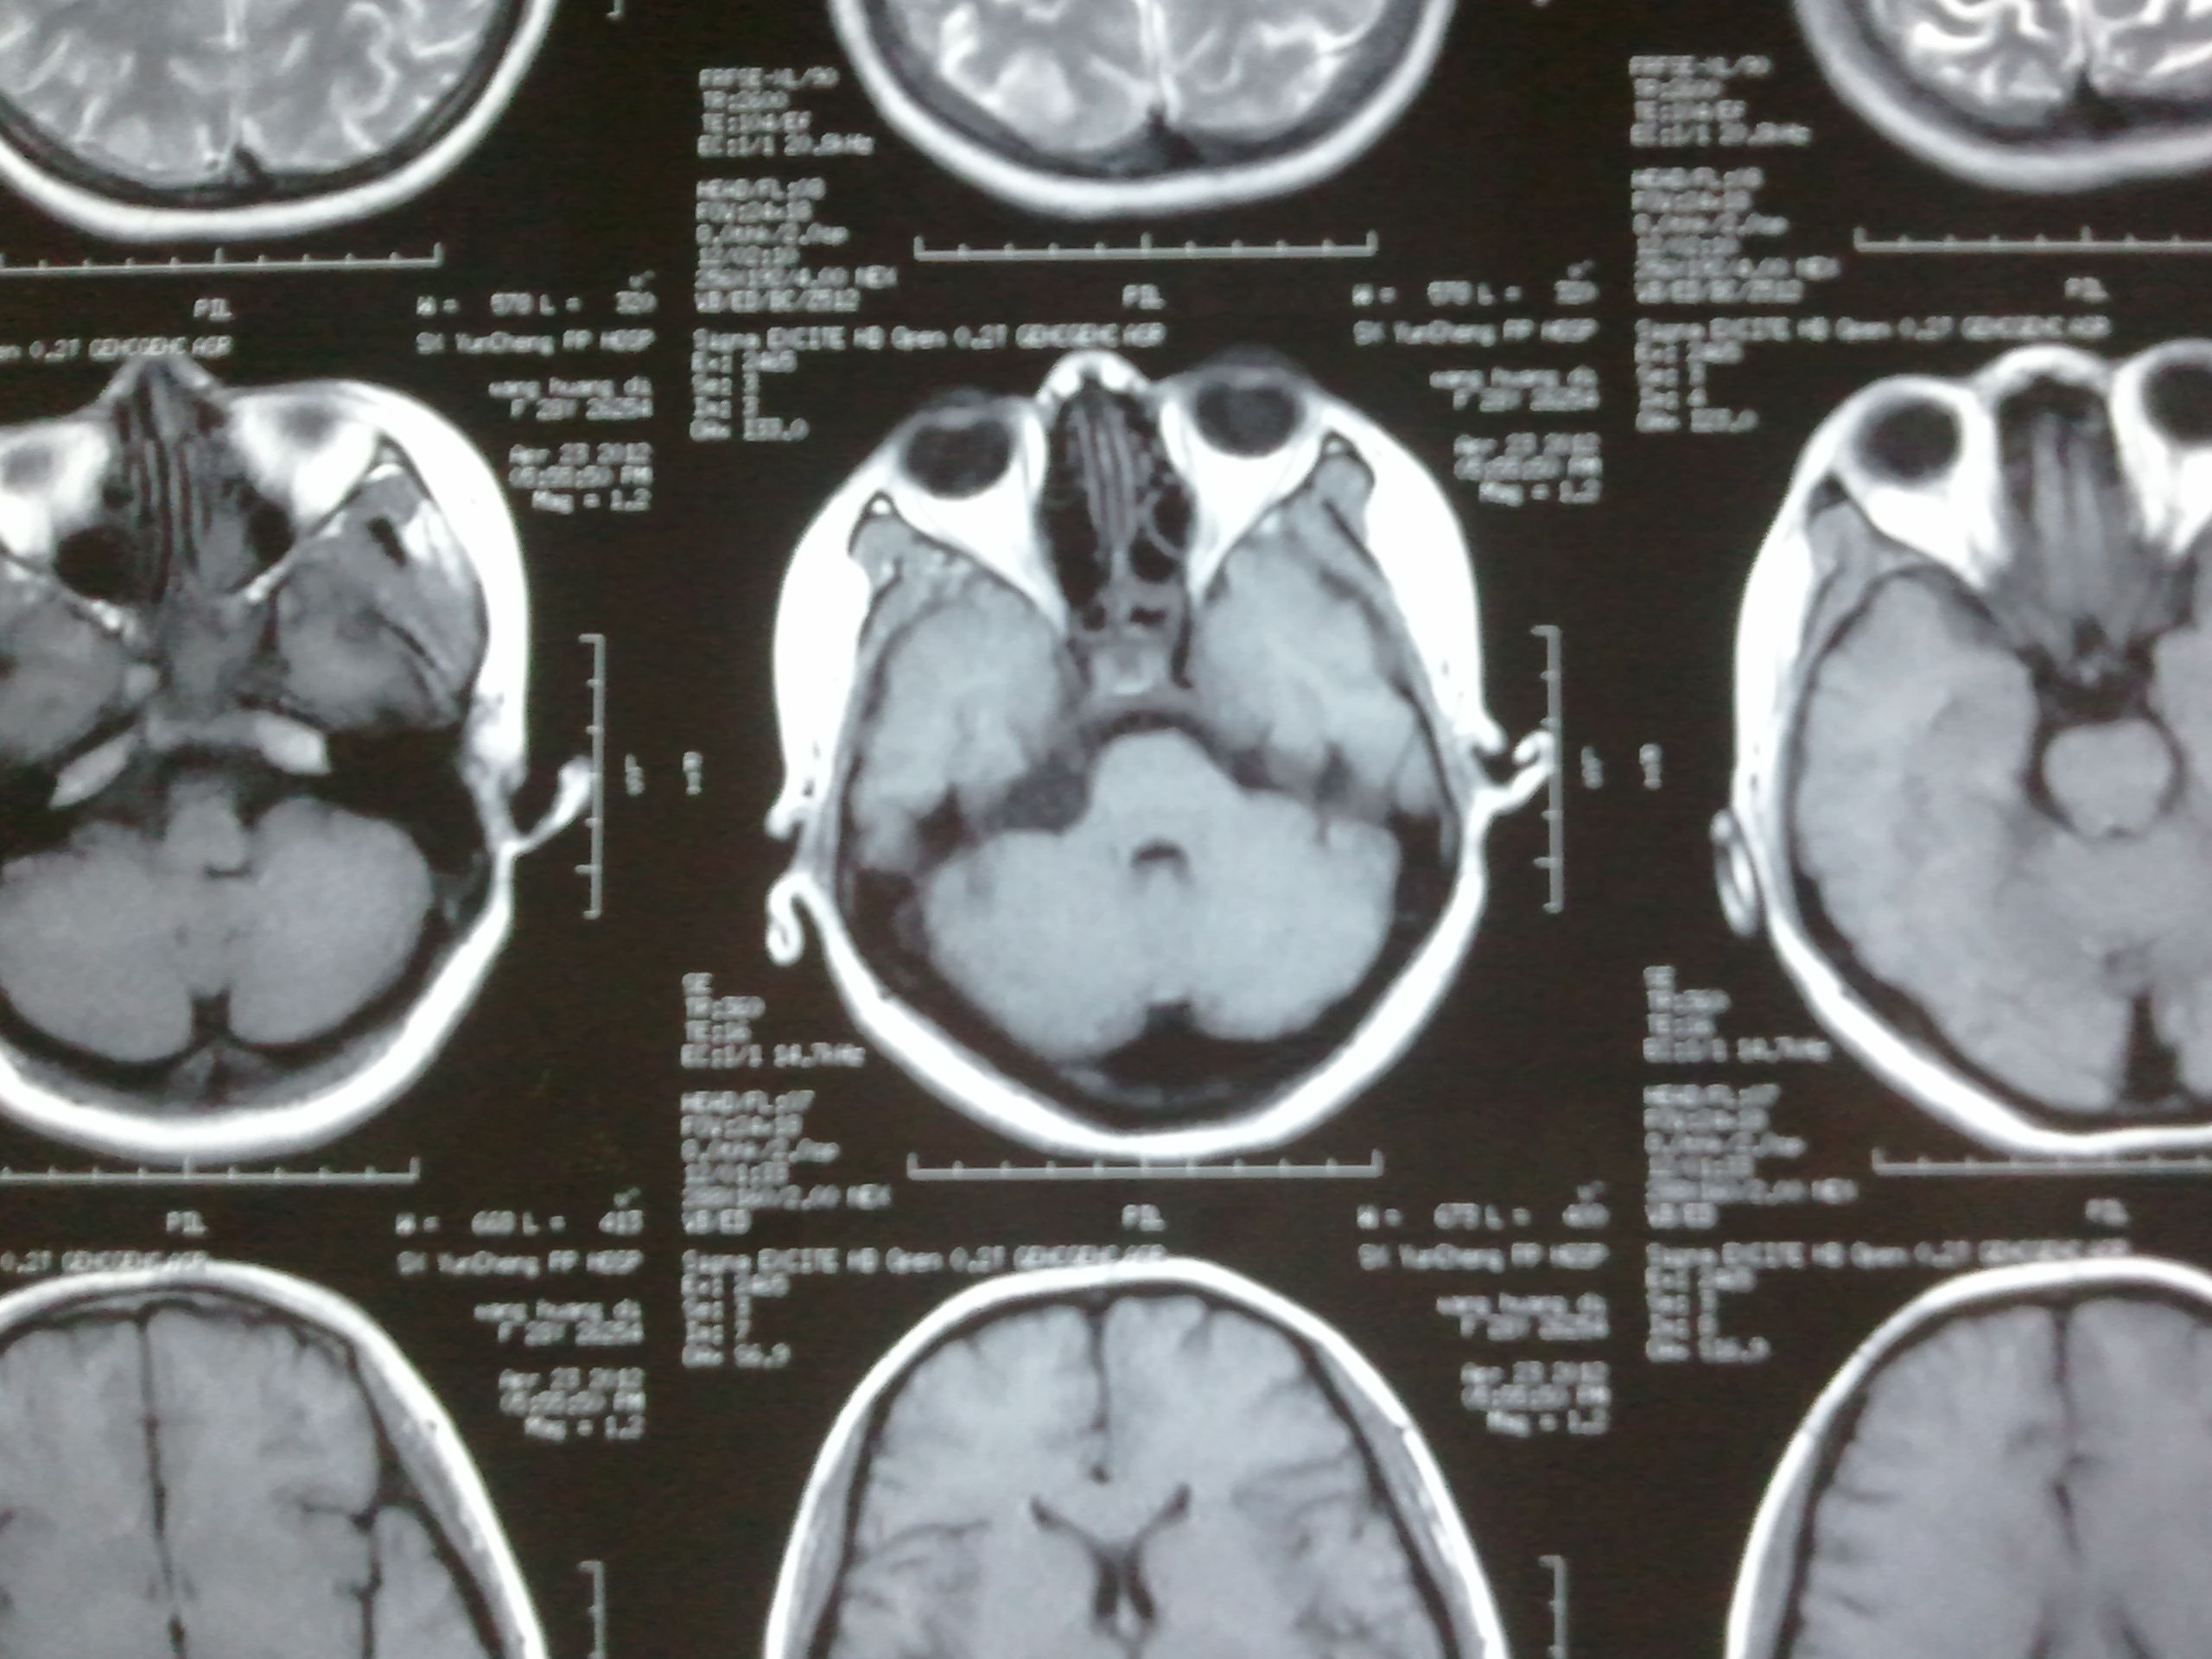

颅内胆脂瘤

图片尺寸410x307